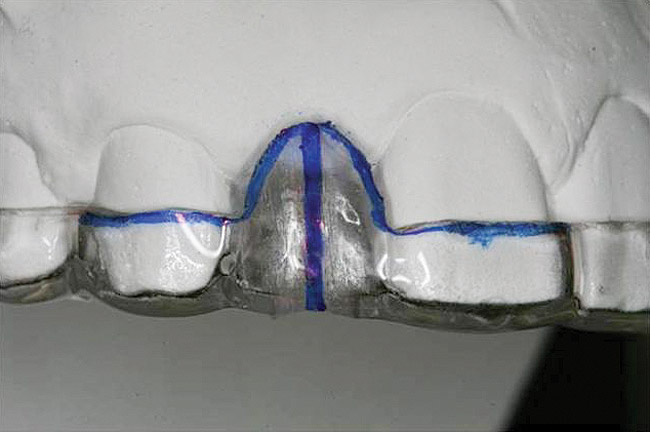

Figure 21   Gingival zenith planning: The location of the gingival zenith for this missing lateral incisor is not fully evident during initial clinical evaluation (Fig 21). Subsequent diagnostic waxing reveals the position of the planned gingival zenith (Fig 22). A thermoplastic template captures the position of the zenith and enables transferring this location to the clinical environment (Fig 23 and Fig 24). Final crown contours are defined by soft-tissue form (Fig 25).

Figure 22  Gingival zenith planning: The location of the gingival zenith for this missing lateral incisor is not fully evident during initial clinical evaluation (Fig 21). Subsequent diagnostic waxing reveals the position of the planned gingival zenith (Fig 22). A thermoplastic template captures the position of the zenith and enables transferring this location to the clinical environment (Fig 23 and Fig 24). Final crown contours are defined by soft-tissue form (Fig 25).